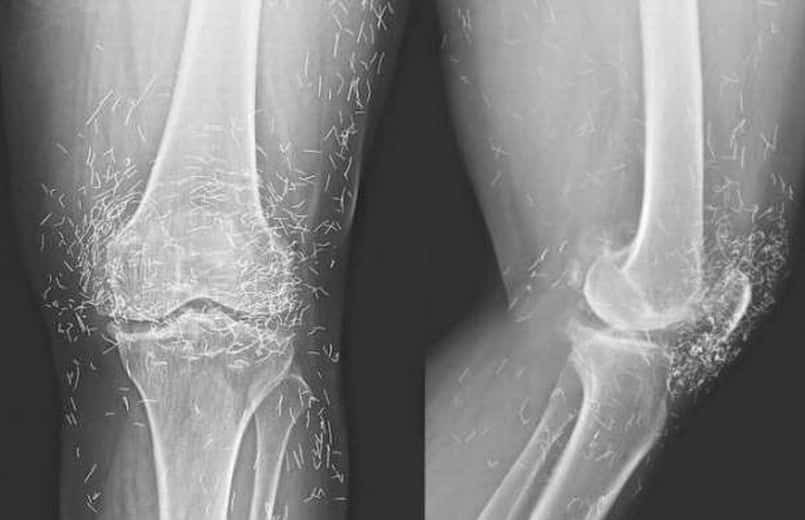

Της συνέστησαν αγωγή με ειδικά φάρμακα αλλά και ενέσεις, οι πόνοι όμως δεν υποχωρούσαν. Μετά από λίγο καιρό τα αντιφλεγμονώδη φάρμακα τις προκάλεσαν και στομαχικές διαταραχές. Ξαναπήγε στο νοσοκομείο και οι γιατροί την υπέβαλλαν σε νέες εξετάσεις. Μια ακτινογραφία έδειξε αυτό το εκπληκτικό. Τα πόδια της είχαν καρφωμένες μέσα, δεκάδες χρυσές καρφίτσες.

Η 65χρονη, προκειμένου να σταματήσει να πονάει είχε απευθυνθεί σε ειδικό βελονιστή. Οι καρφίτσες δεν βγήκαν από το κορμί της ‘ύστερα από οδηγία του βελονιστή αφού εάν παρέμεναν μέσα, θα λειτουργούσαν σαν «μόνιμος» βελονισμός.